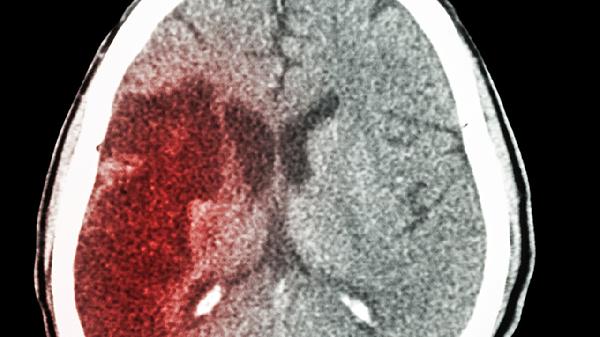

脑溢血多半是洗澡洗出来的?洗澡若出现这3种不适,赶紧去医院!

洗澡时突然头晕目眩,你以为只是低血糖?小心这可能是身体发出的危险信号!最近有研究发现,不当的洗澡方式确实可能诱发脑血管意外,特别是对三高人群来说更要当心。

不同于普通头痛,这种痛感像“被雷劈中”,可能伴随喷射状呕吐。这是颅内压增高的典型表现。